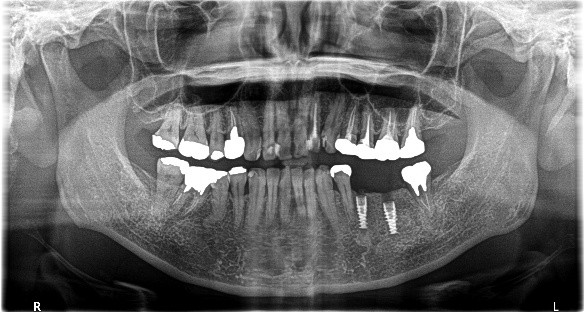

上顎4本残っている歯を抜歯し、インプラントを6本埋入。下顎、右下2本、左下1本埋入。

所感

上顎3本は、もし義歯で対応する場合であれば、保存してマグネット義歯の支台として活用します。しかし、患者さんが義歯ではなくインプラント治療を希望され、かつ、見た目が自然でよく嚙めるようになることが最優先事項でしたので、相談したうえで3本の歯は積極的に抜歯しました。

治療後、「インプラント治療に満足しています。食事が楽しくなりました。スタッフの方の説明がわかりやすかったです。1年間ありがとうございました。」と、とてもうれしくなる感想を書いていただきました。

上顎:全額治療 ¥3,280,000(税込)

下顎:インプラント3本 ¥363,000×3本=¥1,089,000(税込)

合計:¥4,369,000(税込)

Before

After